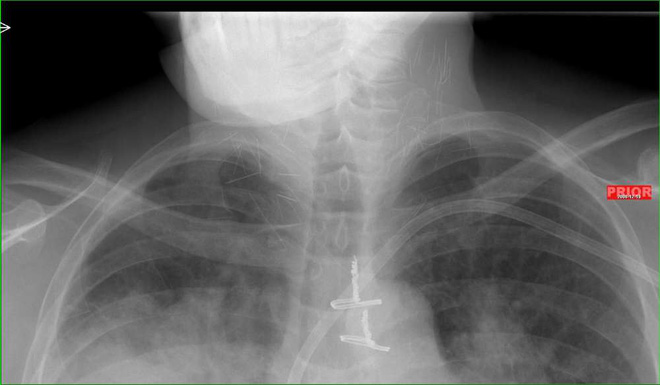

Mới đây một hình X-quang đã được chia sẽ lên mạng. Nhiều người nhìn bức hình đã phải giật mình. Trong cơ thể người nghiện có rất nhiều mũi kim.

Và mới đây, một bức hình chụp X-quang phần cổ của một con nghiện heroin lâu năm đang được chia sẻ với tốc độ chóng mặt. Quan trọng hơn, ai nhìn thấy nó cũng phải rùng mình.

Bạn có quan sát thấy những đường thẳng chi chít ở 2 bên cổ không? Bạn nghĩ đó là gì? Câu trả lời là những mũi kim tiêm.

Theo đó, bệnh nhân là một con nghiện heroin lâu năm, đến bệnh viện trong tình trạng viêm phổi nặng. Nhưng đến khi đưa vào máy chụp X-quang, người ta phát hiện ra hàng tá mũi kim gãy vẫn còn trong cổ anh ta.

Theo thông tin từ vị bác sĩ, bệnh nhân này có vẻ như đã sử dụng heroin bằng cách tiêm chích. Khi tiêm vào cổ, thuốc lên quá nhanh khiến anh ta mất ý thức, buông tay và làm gãy kim tiêm.

Ví dụ như vào năm 2006, trang tin từ công ty y dược UBM Patient Care đã đăng tải trường hợp của một bệnh nhân 53 tuổi, có tiền sử lạm dụng heroin trong 30 năm. Và bên trong cổ của ông có tới 17 mũi kim gãy.

"Kim gãy và lưu lại trong cơ thể khi tiêm ma túy là hiện tượng không hiếm" - một bác sĩ từ công ty cho biết. "Từng có một nghiên cứu cho thấy có thể 20% con nghiện heroin đã trải nghiệm cảm giác kim gãy khi đang tiêm chích".